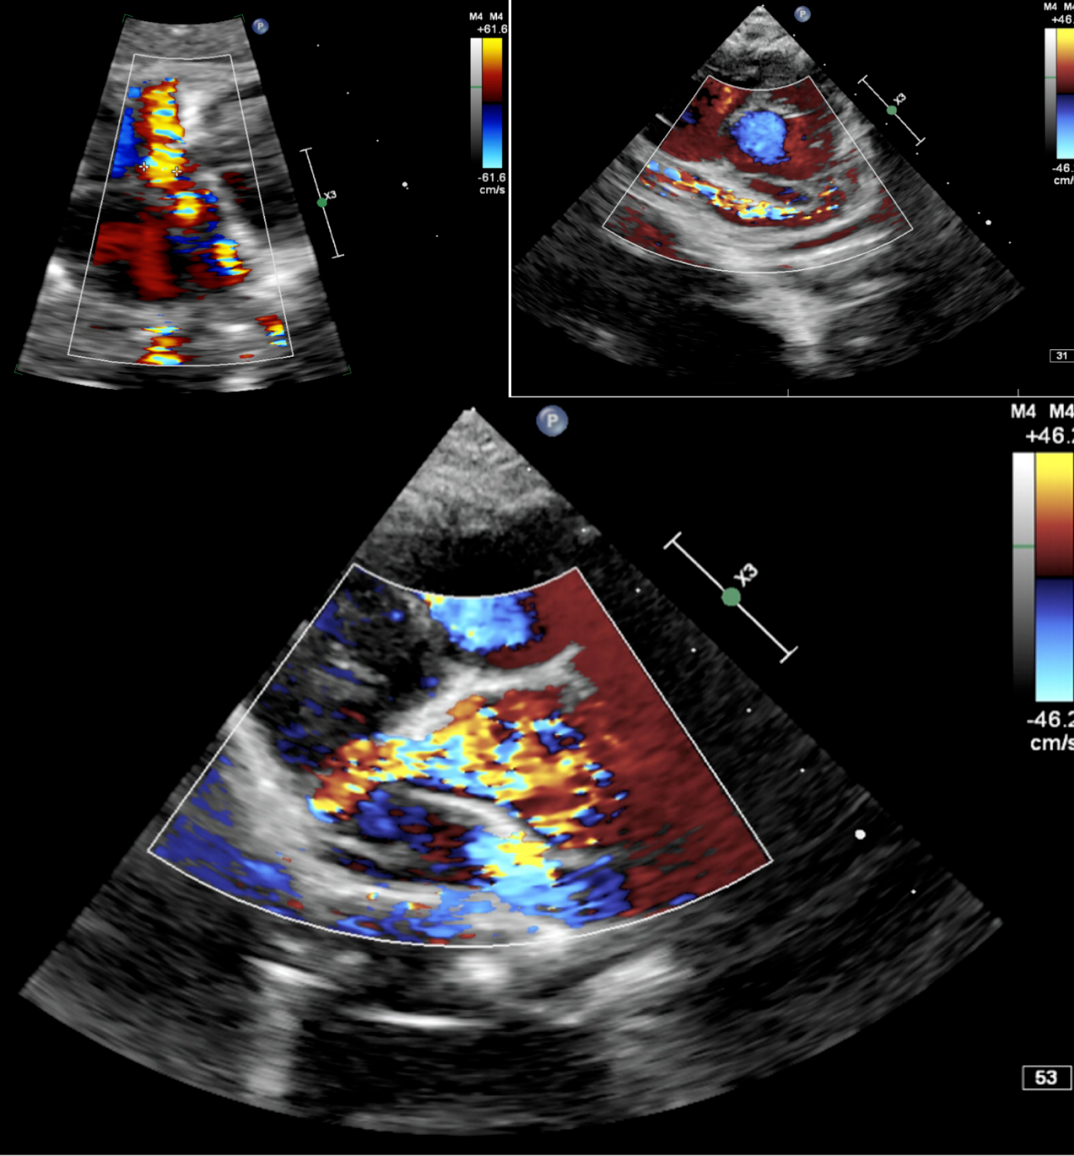

术中造影提示左冠状动脉及回旋支明显增粗,回旋支发出一粗大的瘘血管与冠状静脉窦联通,瘘口处存在多处狭窄。

图片

通过5F左冠造影管将0.032 in超滑导丝260 cm通过瘘口,进入下腔静脉后,使用网篮抓捕导丝建立轨道。